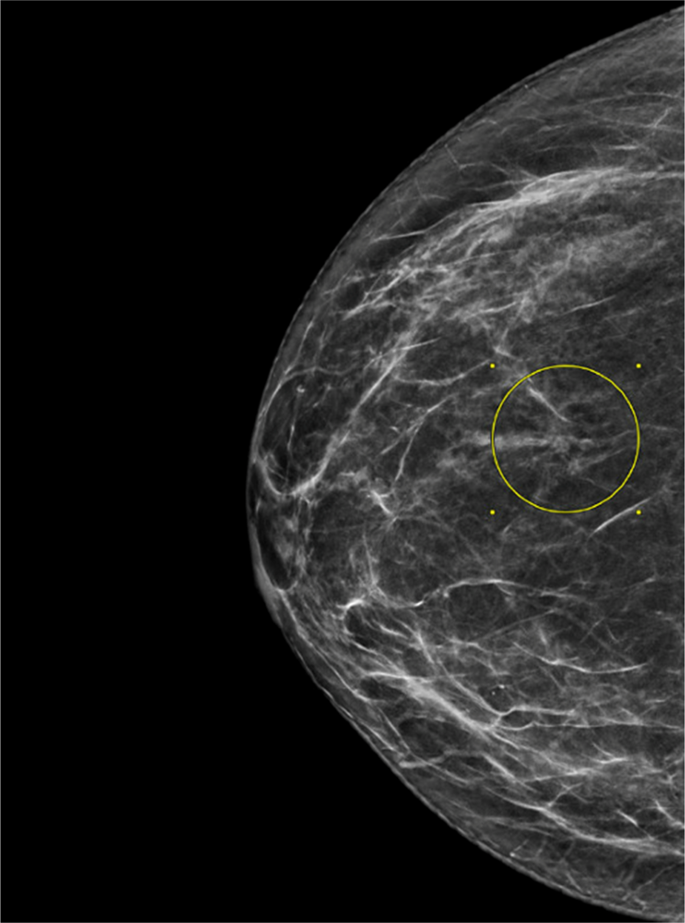

Mammographically detected architectural distortion (AD) of the breast is defined as a localized alteration in the uniform texture of the breast characterized by lines radiating from a central point, without the formation of a mass (Fig. 1)1. AD is the third most common screen-detected abnormality associated with cancer on mammography after masses and calcifications; however, it represents just 6% of screen-detected abnormalities2. Areas of AD are distinct from masses on mammography because a central density is often absent and there are no definable outward convex margins. AD may be present as a solitary finding or can be associated with additional imaging findings on mammography, ultrasound (US), or MRI.

There has been an increase in the detection of AD with the introduction of digital-breast tomosynthesis (DBT), which was approved by the United States Food and Drug Administration in 2011. DBT reduces the superimposition of fibroglandular tissue, which helps to visualize findings that otherwise might be obscured. Therefore, the subtle architectural changes and radiating lines that can indicate an underlying AD and be occult on 2D mammography may be more easily identified with tomosynthesis3,4,5,6.